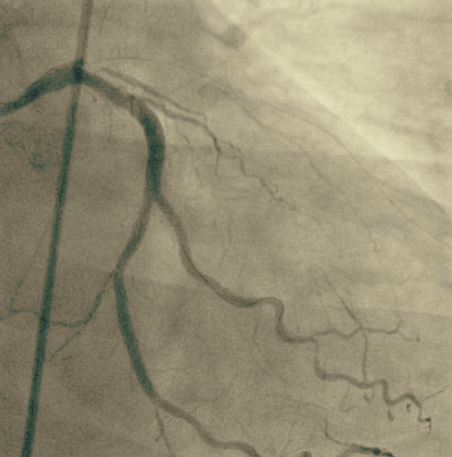

Wiedereröffnetes Gefäß

Die wichtigste Therapie der koronaren Herzerkrankung besteht in der Aufweitung verengter Herzkranzgefäße (Ballonangioplastie/PTCA) und der Implantation von Gefäßstützen (Stents). Hierbei kommen zur bestmöglichen Versorgung unserer Patienten medikamentenbeschichtete Stents zum Einsatz. Besonders schwer verkalkte Herzkranzgefäße können auch mit einem kleinen Bohrkopf wieder erweitert werden (Rotablation).

Ein besonderer Schwerpunkt in unserer Klinik liegt auf der Versorgung komplexer Mehrgefäßerkrankungen, einschließlich Hauptstamminterventionen. Darüber hinaus werden aber auch chronisch verschlossenen Gefäße (CTO) rekanalisiert. Auf diese Weise können teilweise Bypass-Operationen vermieden werden.